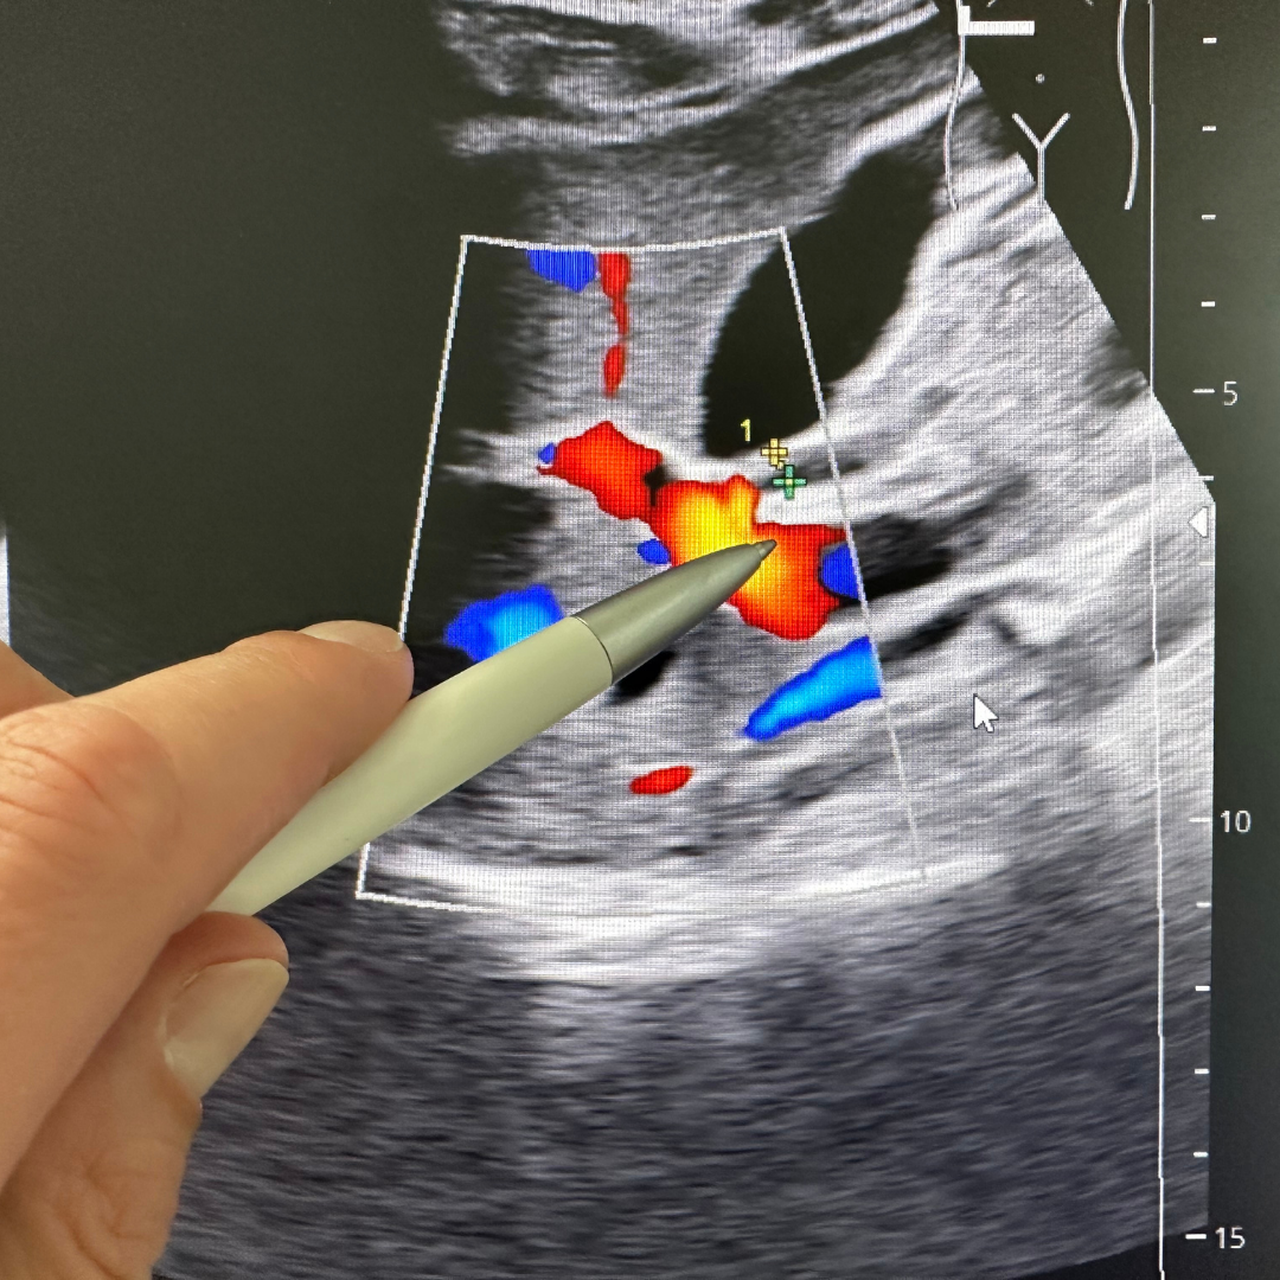

Ung thư đường mật (cholangiocarcinoma) là một loại ung thư hiếm gặp, khởi phát từ các tế bào biểu mô lót trong hệ thống đường mật - ống dẫn mật bên trong và bên ngoài gan. Đây là nhóm bệnh lý ác tính có tiên lượng xấu do thường được phát hiện muộn, khi khối u đã phát triển hoặc lan rộng, gây khó khăn trong việc điều trị triệt để.

Bệnh có thể phân loại dựa trên vị trí khối u, bao gồm: Ung thư đường mật trong gan (intrahepatic), ung thư vùng rốn gan (perihilar, còn gọi là Klatskin tumor) và ung thư đường mật ngoài gan xa (distal extrahepatic). Mỗi thể có đặc điểm lâm sàng, phương pháp chẩn đoán và cách điều trị khác nhau, nhưng đều liên quan chặt chẽ đến tình trạng tắc nghẽn đường mật.